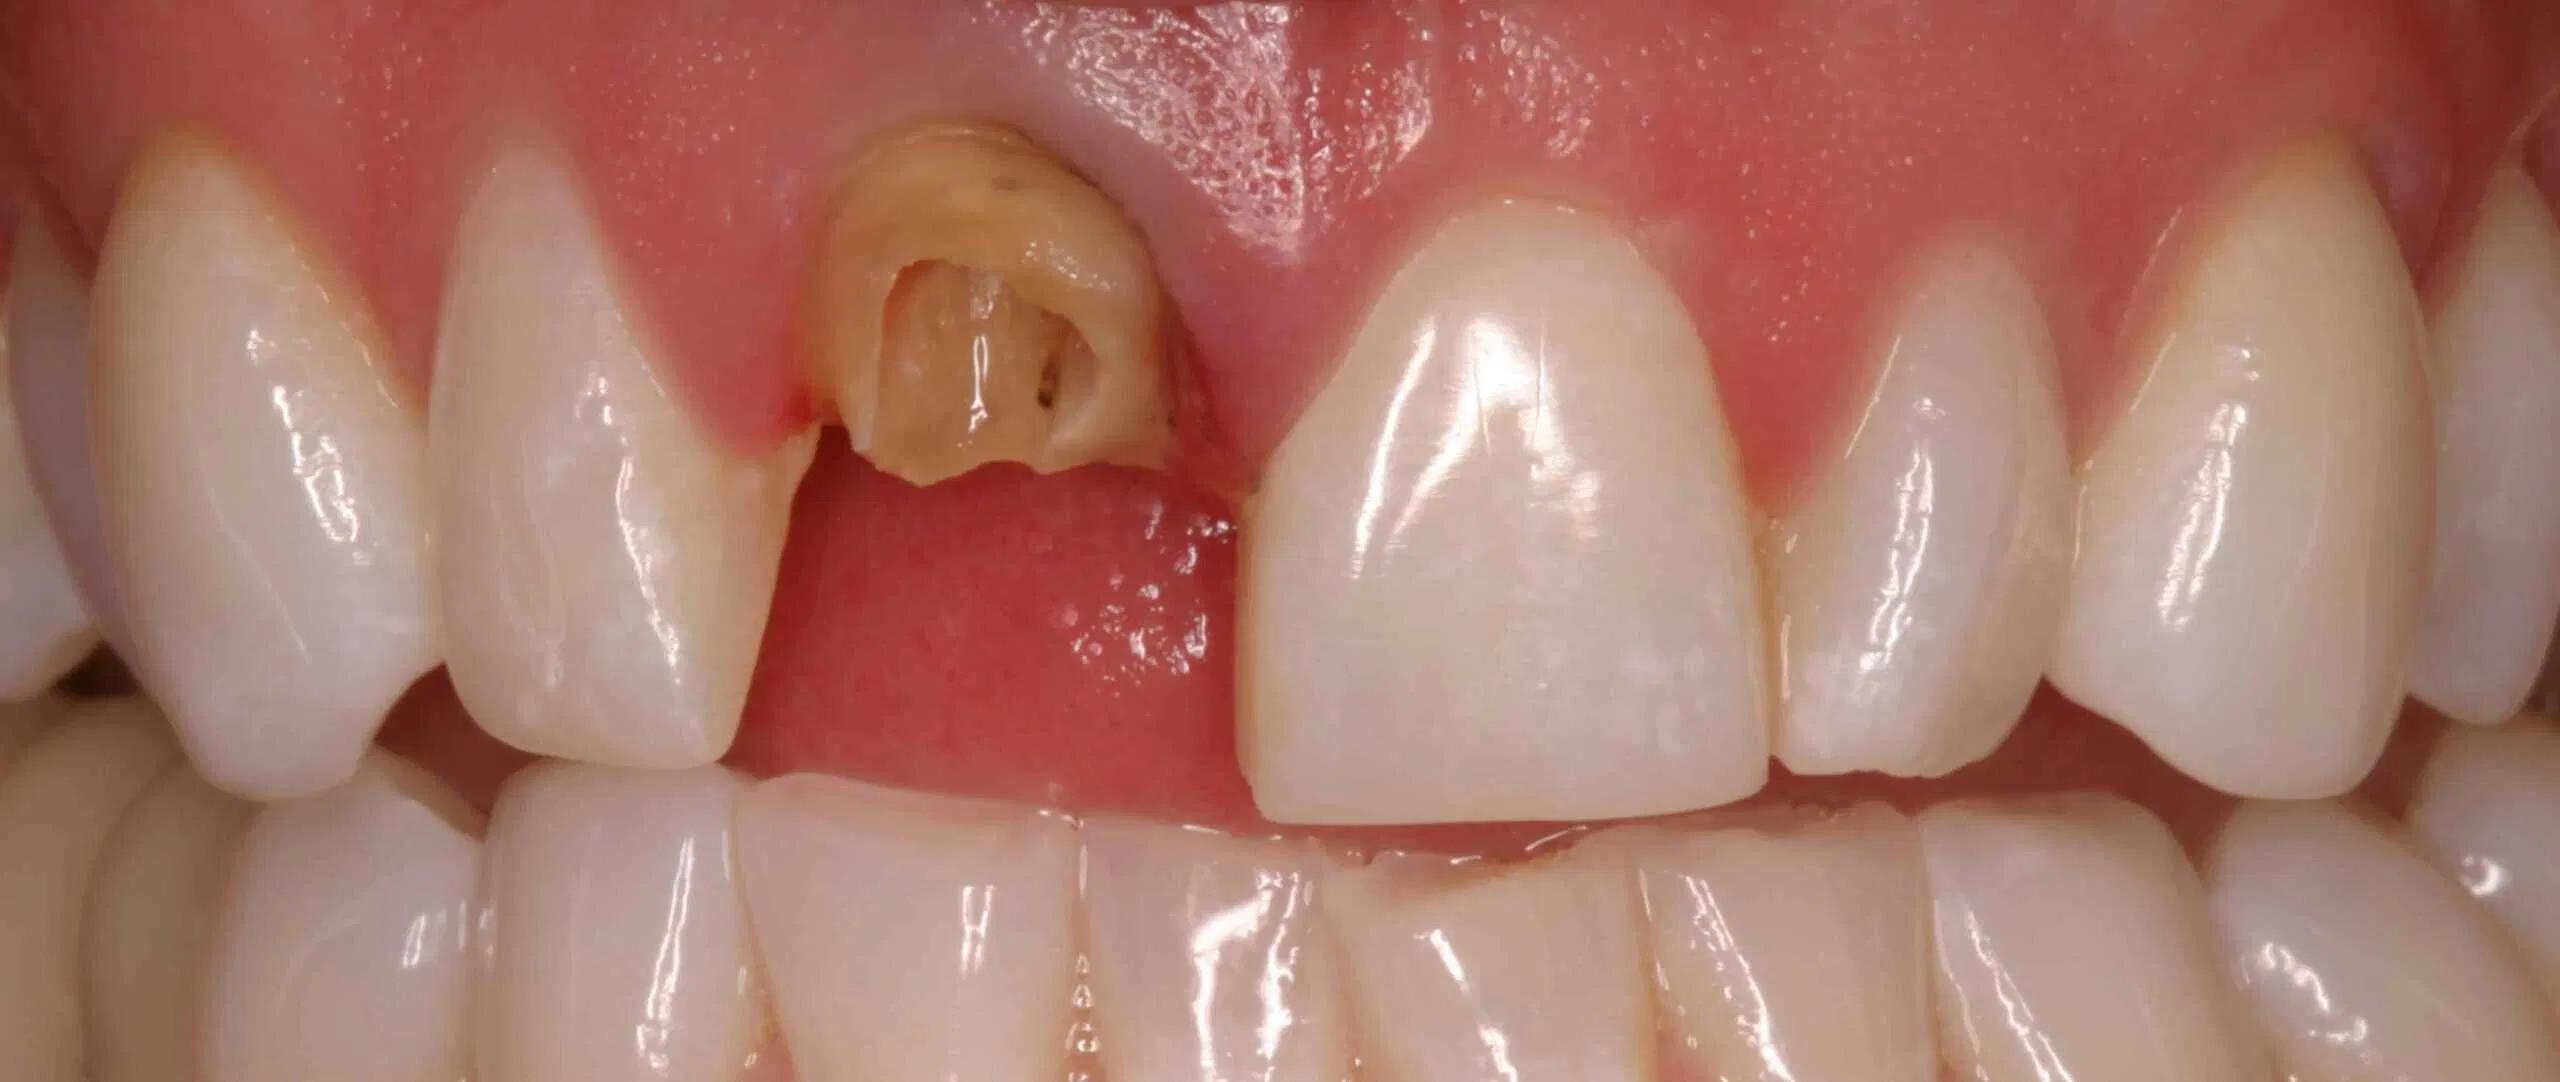

Before:Â Fractured/failed heavily treated upper right central incisor (tooth #8). The root is non-restorable and requires removal. The treatment of choice is a single implant supported restoration.

After: Single, all-ceramic crown attached to an all-ceramic, CAD-CAM designed and generated abutment (implant post). A delayed treatment approach was undertaken: tooth/root removal and grafting; 4 months healing; interim removable partial tooth replacement; implant placement; 6 months healing; proto-type (transitional fixed) implant crown, then the definitive implant restoration. The new tooth blends in perfectly with the natural, adjacent teeth.